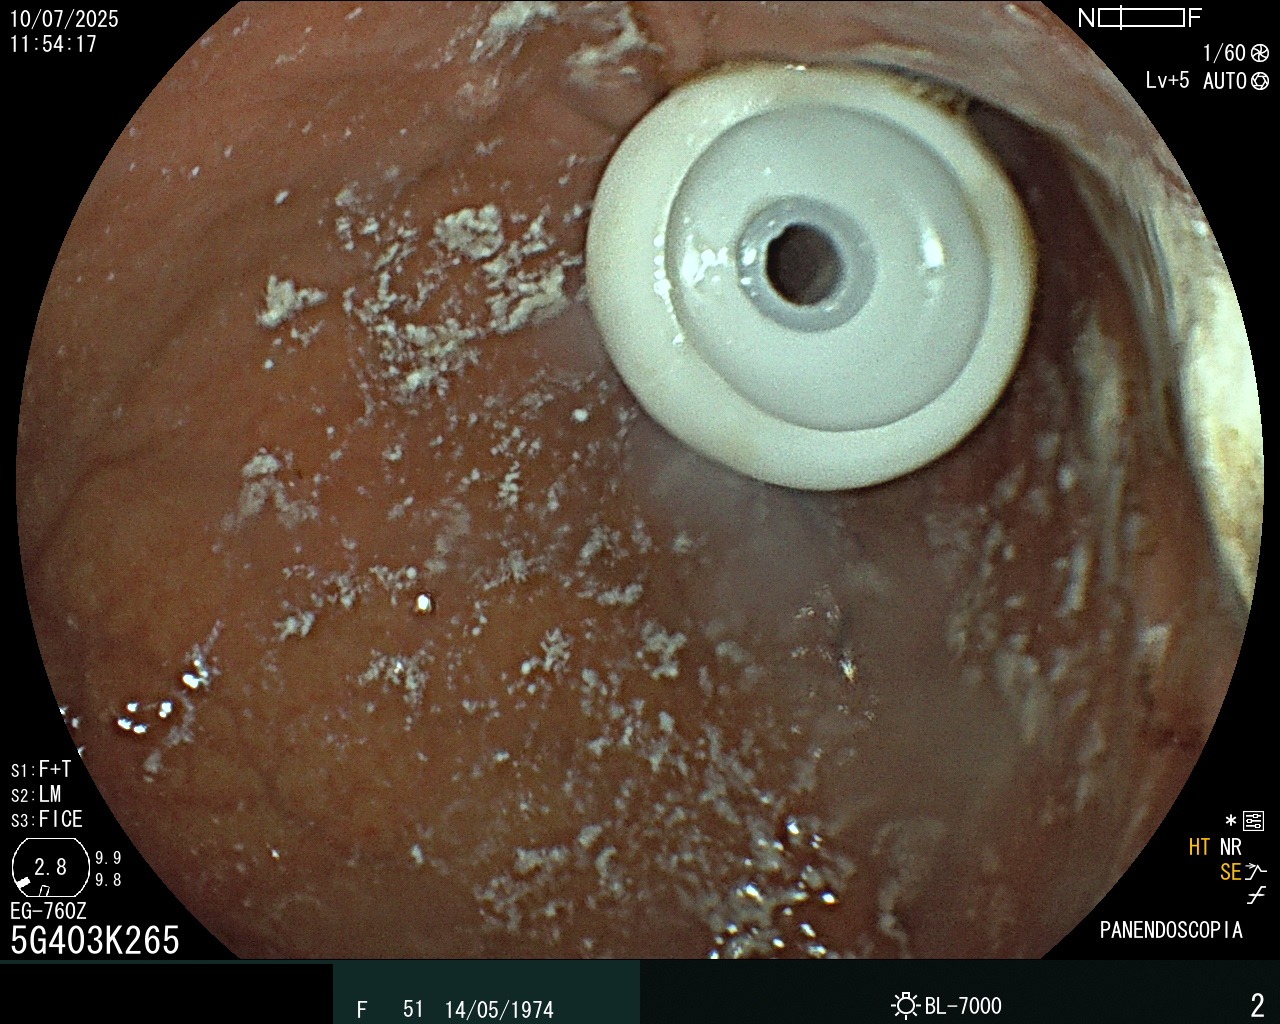

Gastrostomía

Procedimiento de gastrostomía endoscópica